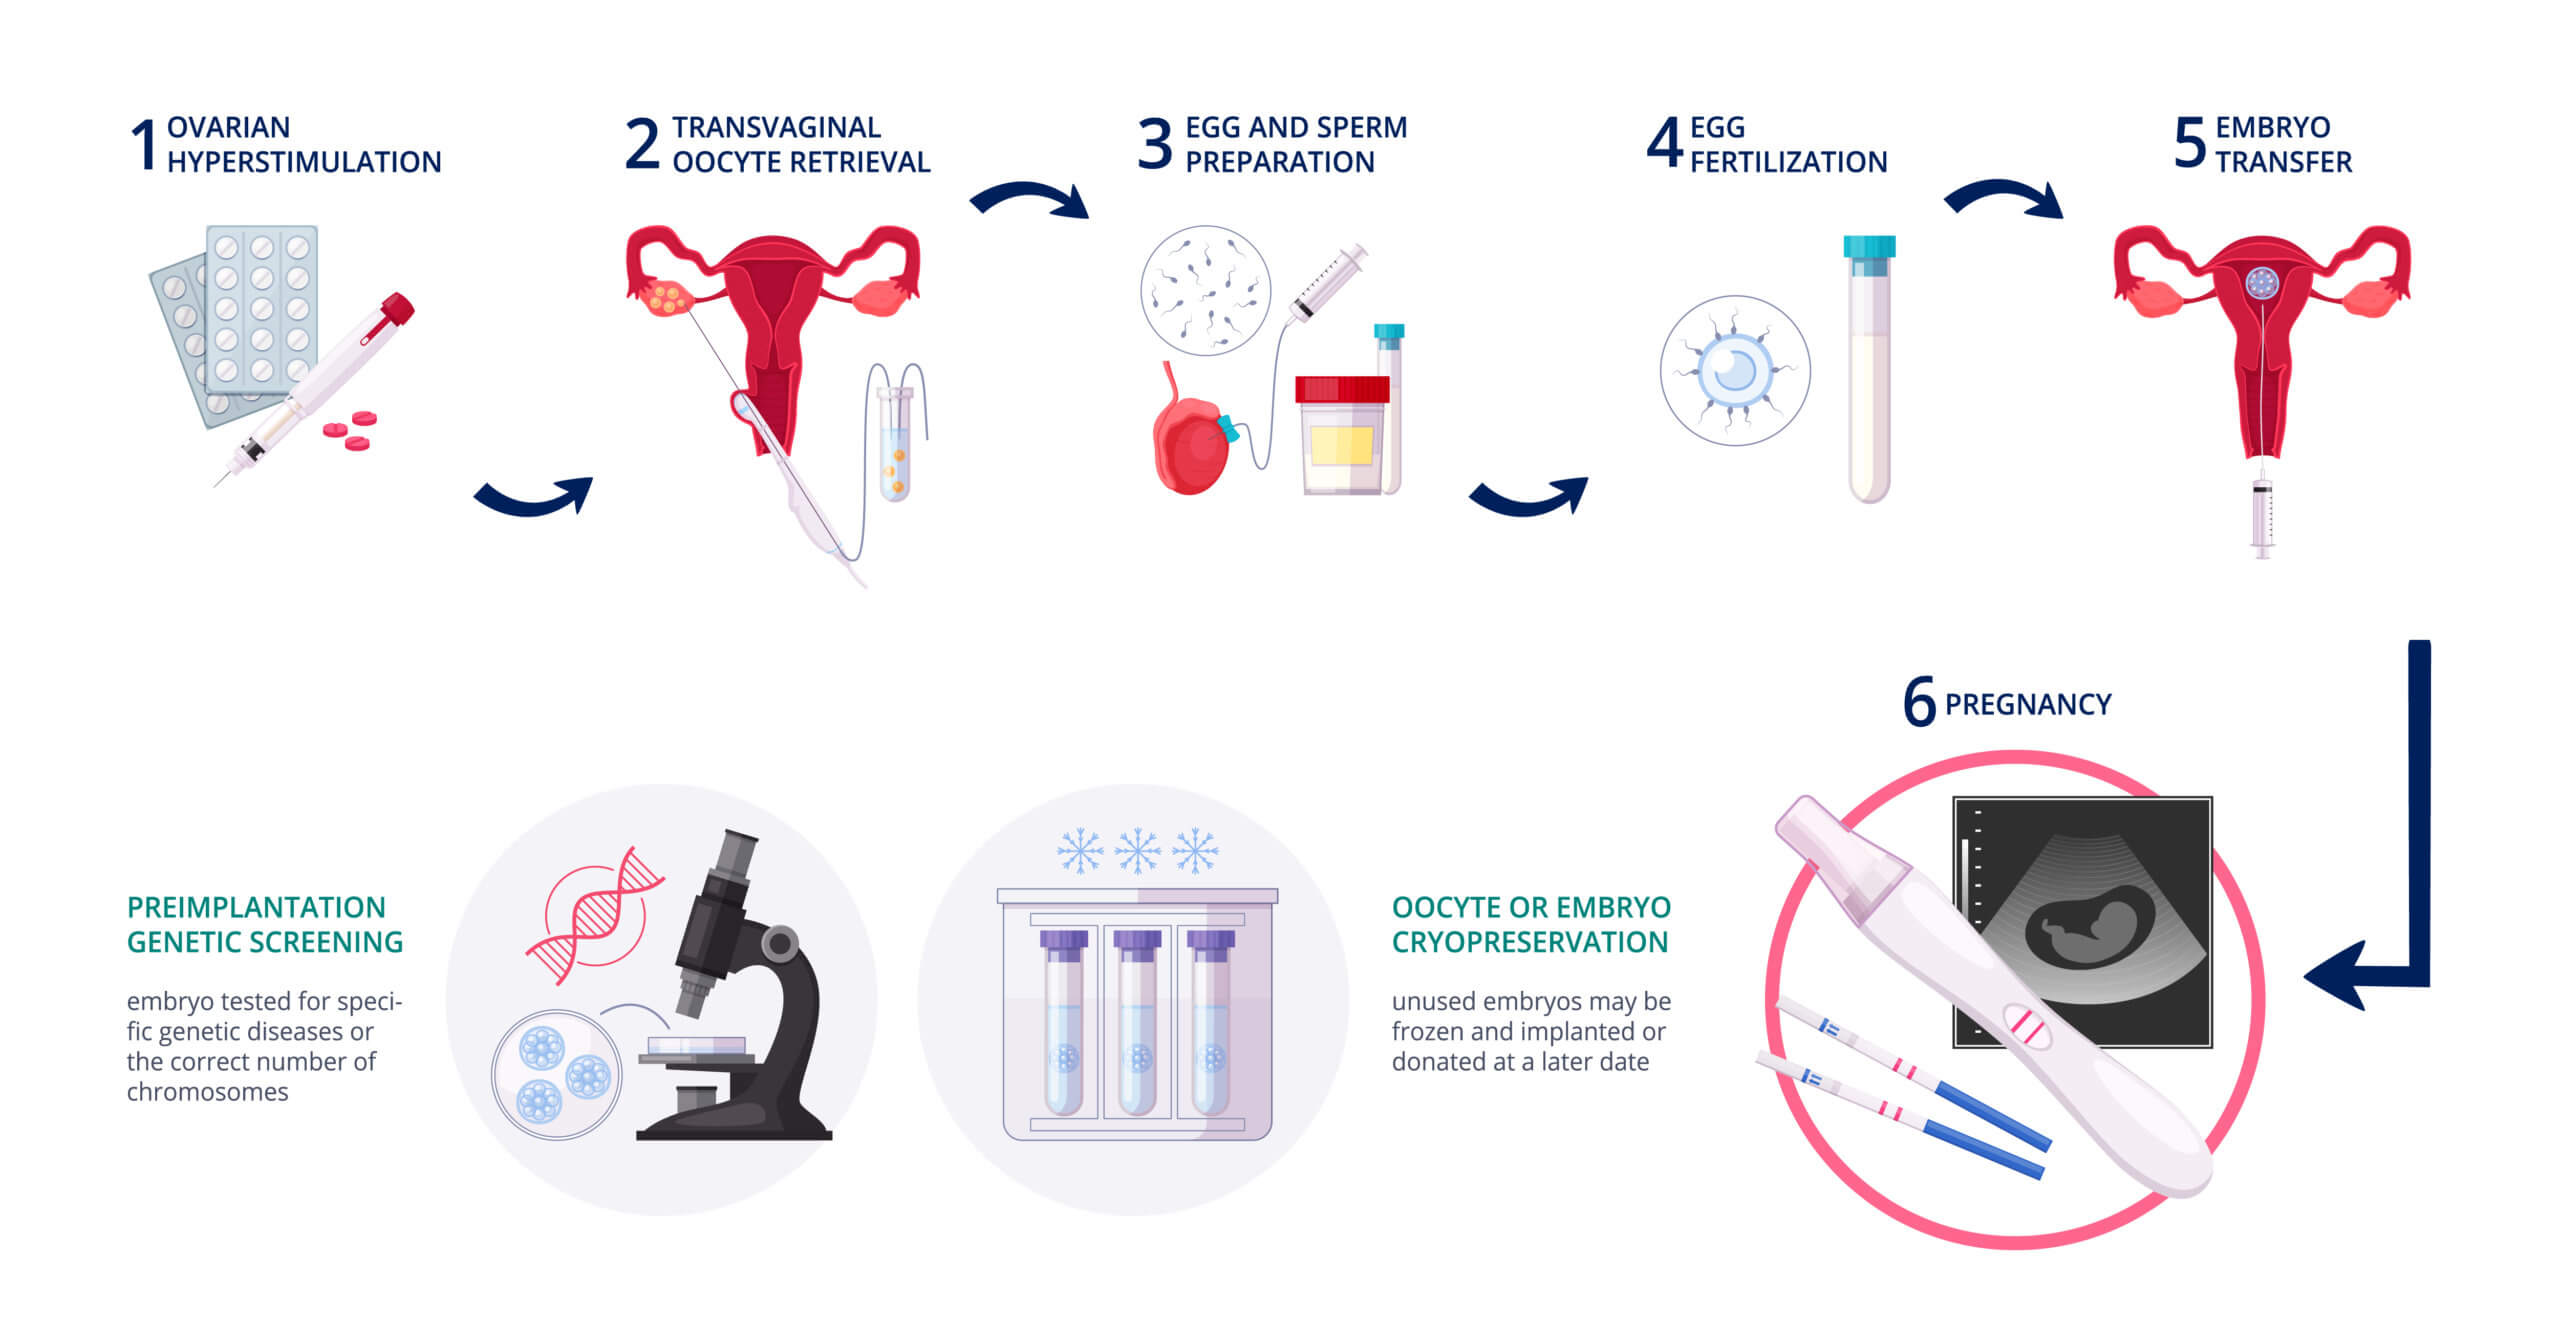

IVF Step by Step

The following are IVF steps:

-

Stimulate the ovarian for two weeks -

Collect (retrieve) oocytes from the woman’s uterus -

Collect sperm from semen -

Bring together the oocyte and the sperm in a laboratory dish -

Wait for a couple of days until the oocyte is fertilized and begins cell division (becomes an embryo) -

Put back the embryo inside the woman’s uterus (embryo transfer)

More than one egg can get fertilized at the same time.

Also, the transfer phase can comprise one or more inside the woman’s uterus, and freeze the rest. In case the IVF attempt did not work, the patient can repeat only the last step.